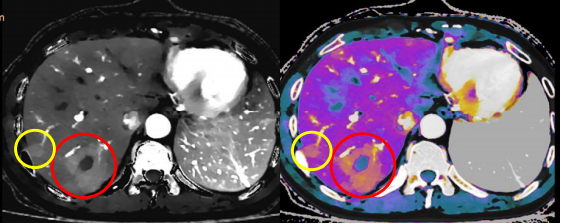

在肿瘤成像方面,皓克光谱CT能提供全面快速的肿瘤全程评估,覆盖肿瘤早期发现、精准分期和疗效评估,优势明显。它可以更早捕获组织成分上的微小变化,能够尽早发现和诊断早期隐匿性肿瘤病灶。利用光谱曲线、碘定量测量等多参数分析技术,该CT还可准确分析肿瘤的良恶性、多发病灶的同源性,进而应用于肿瘤来源的判断和鉴别、良恶性肿瘤的鉴别以及恶性肿瘤的分级,确定淋巴结是否有转移等。